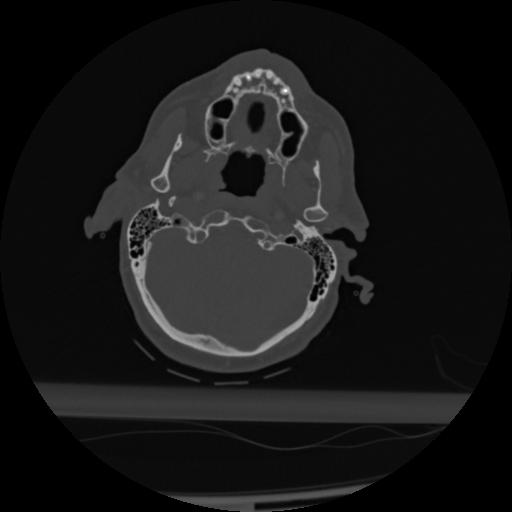

22 ANGIO,CE,Vol,0.5,ANGIO,,